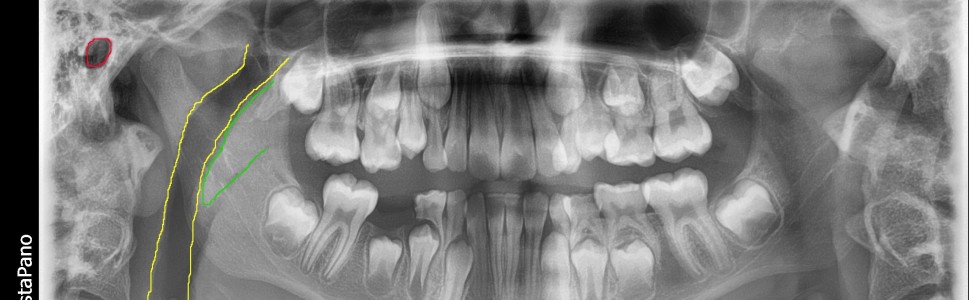

Zdjęcie pantomograficzne. Kolor niebieski – cień rzeczywisty podniebienia twardego strony prawej. Kolor czerwony – cień rzeczywisty podniebienia twardego strony lewej. Kolor żółty – cień wtórny podniebienia twardego strony prawej. Kolor zielony – cień wtórny podniebienia twardego strony lewej.